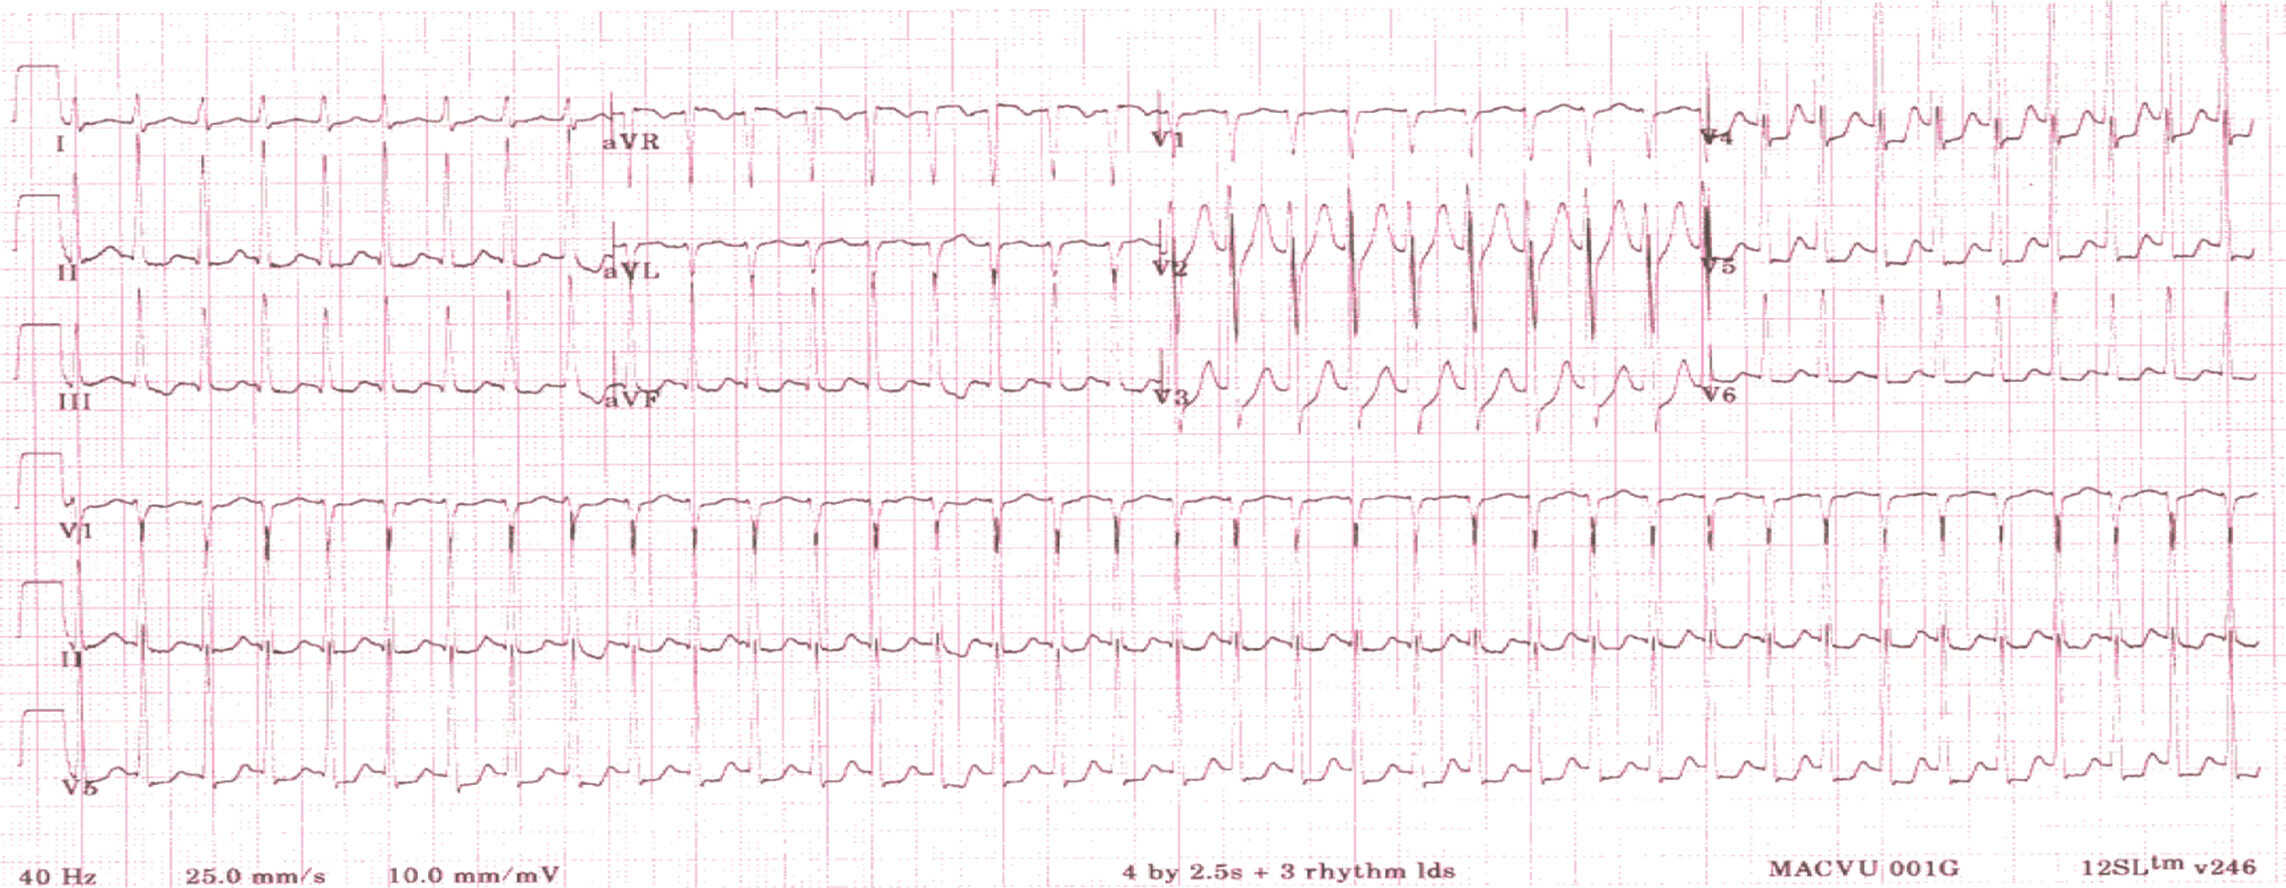

- pour la tachycardie ventriculaire, il s’agit d’une tachycardie à complexes larges (car elle naît en aval de la bifurcation du faisceau de His), tachycardie régulière, avec trois signes ECG typiques : la dissociation atrioventriculaire (plus de QRS que d’ondes P) et les complexes de capture et de fusion (fig. 6.23). Elle est généralement monomorphe, mais peut être polymorphe,

________________________________________________________________________________

Figure 6.23. Tachycardie ventriculaire.

Tachycardie régulière à QRS large monomorphe avec dissociation atrioventriculaire (flèche) et complexes de capture-fusion (flèche en pointillé).